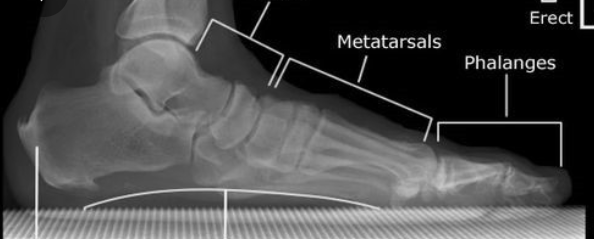

정확한건 X-ray를 찍어서 발바닥 내측 아치가 무너져있는것을 확인해야 진단이 가능합니다.

두번째 그림이 정상적인 발이고 세번째 그림이 내측 아치가 무너져있는 사람의 X-ray 입니다.